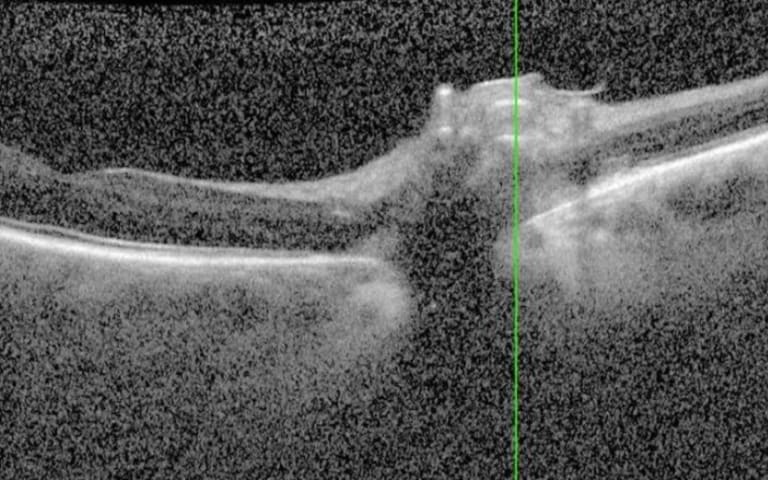

Abb. 3: OCT-Aufnahme des rechten Auges mit Zunahme der Papillenschwellung und neu aufgetretenen Aderhautfalten bei Diagnosestellung 2023.